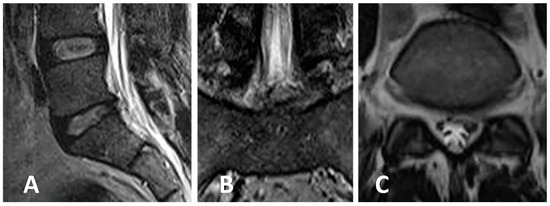

3.3. Clinical Case 1